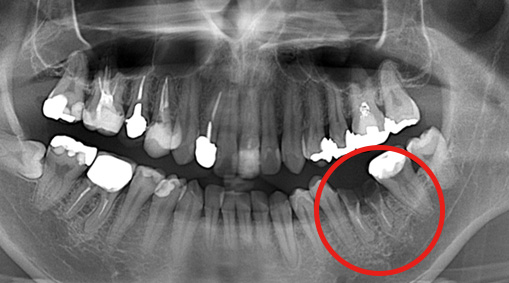

パノラマX線写真

デンタルX線写真う蝕(虫歯)も大きく、治療困難、抜歯が適応です。